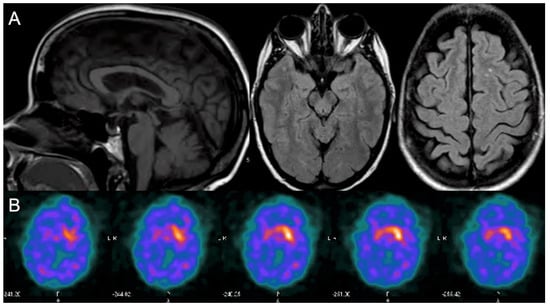

2. Case Report